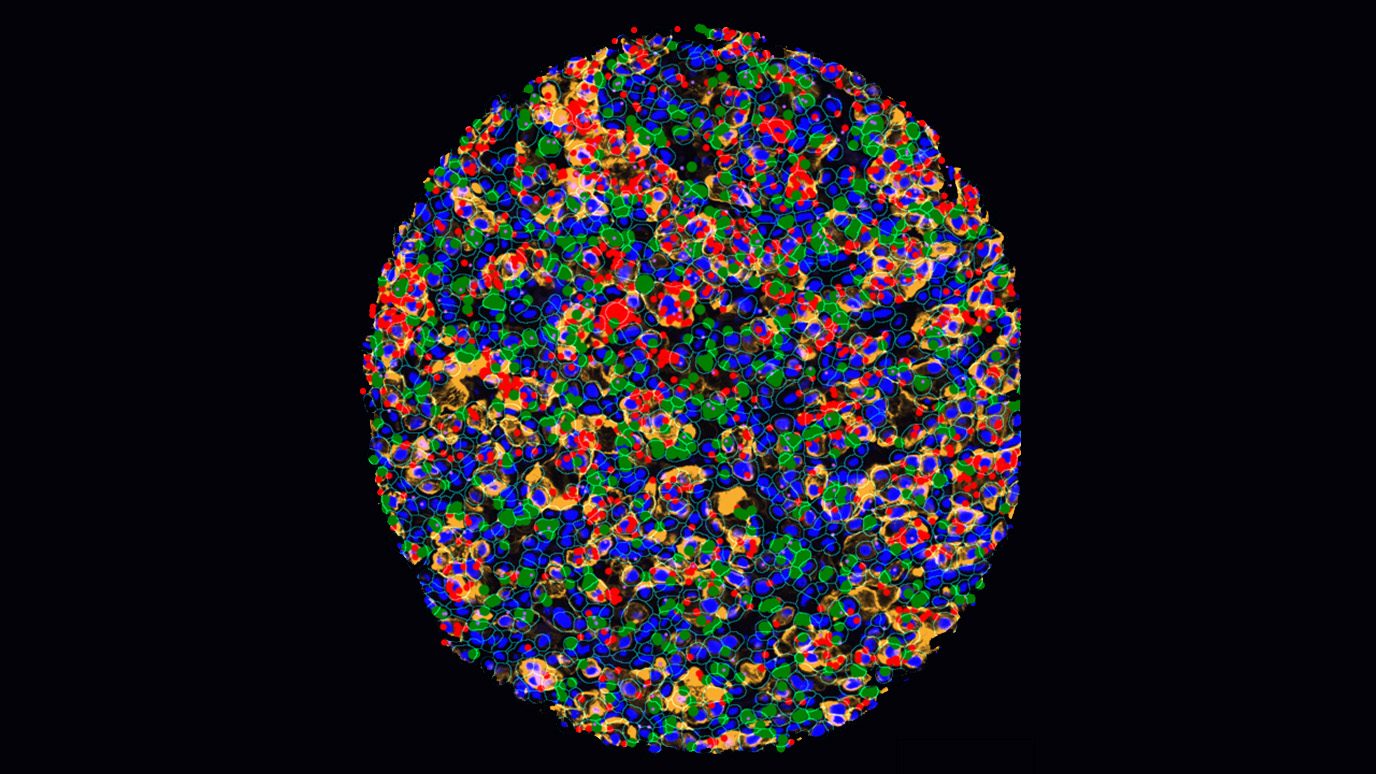

AACR: Single-cell study uncovers distinct immunosuppressive tumor microenvironment in brain metastases from kidney cancer

In a new study, researchers from The University of Texas MD Anderson Cancer Center created the largest single-cell atlas...